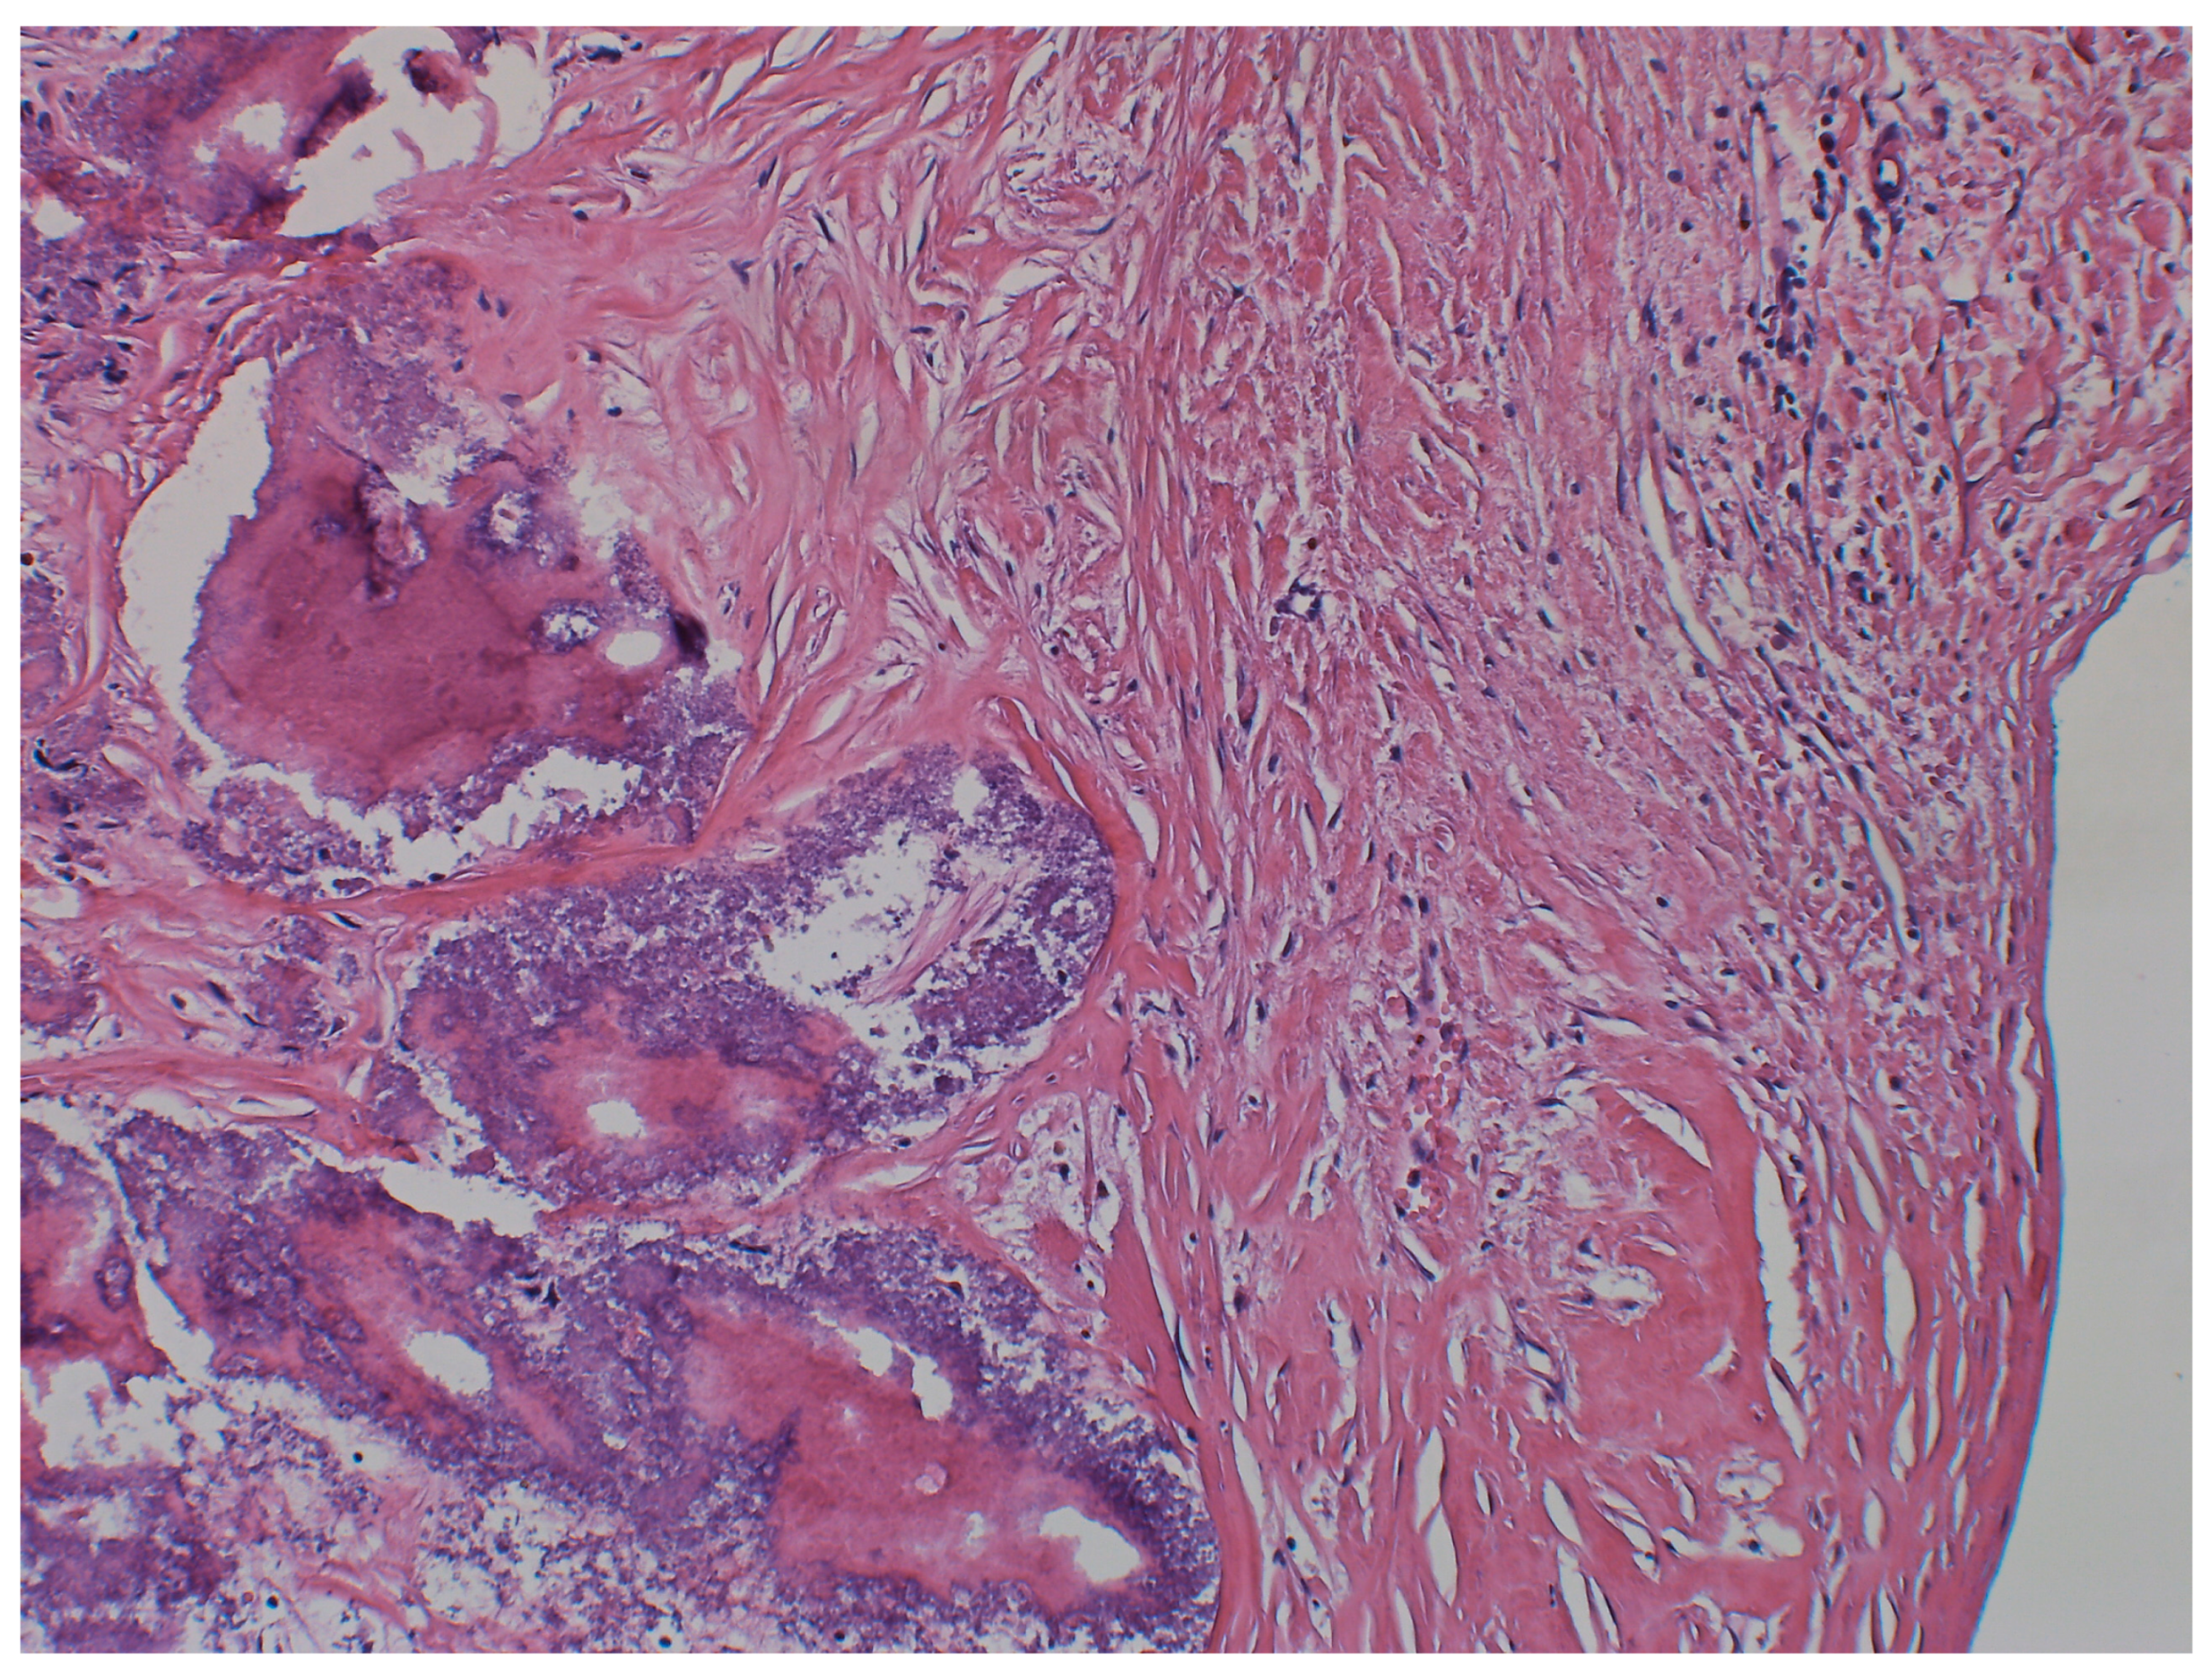

2. Case Presentation